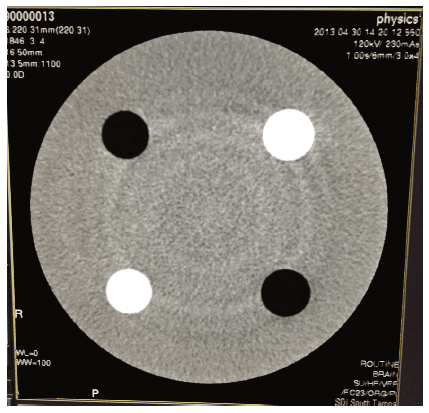

À FAIRE : effectuez tous les scans de contrôle qualité. L’achèvement des scans de contrôle qualité permettra de vérifier l’installation correcte du tube et le fonctionnement du système de scanner.